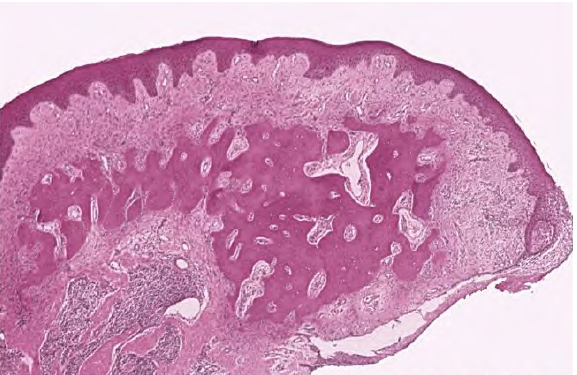

Peripheral Ossifying Fibroma

Histology

What is this clinical finding?

Peripheral Giant Cell Granuloma

Giant cells inside the lesion